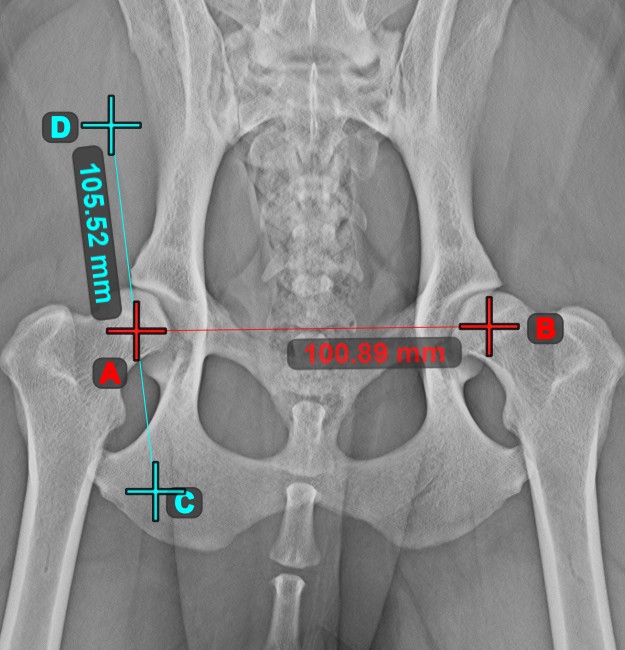

Line Measurement¶

Select the Line Measurement

tool and assign it to one of the available mouse buttons. Place the start and end points on the scene or select them from already existing points on the image. The distance between the two points will be automatically

calculated by using the default calibration data, or the recalibrated data by the length calibration measurement.

Modify the start and end point by using the Select/Move Item

tool. The distance between the two points will be automatically recalculated.